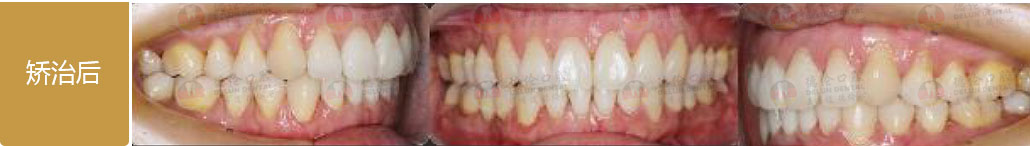

矯治前后對(duì)比

蛻變周期:上頜16個(gè)月,矯治效率提升30%,下頜12個(gè)月,矯治效率提升20%

矯

治

后

口

內(nèi)

照